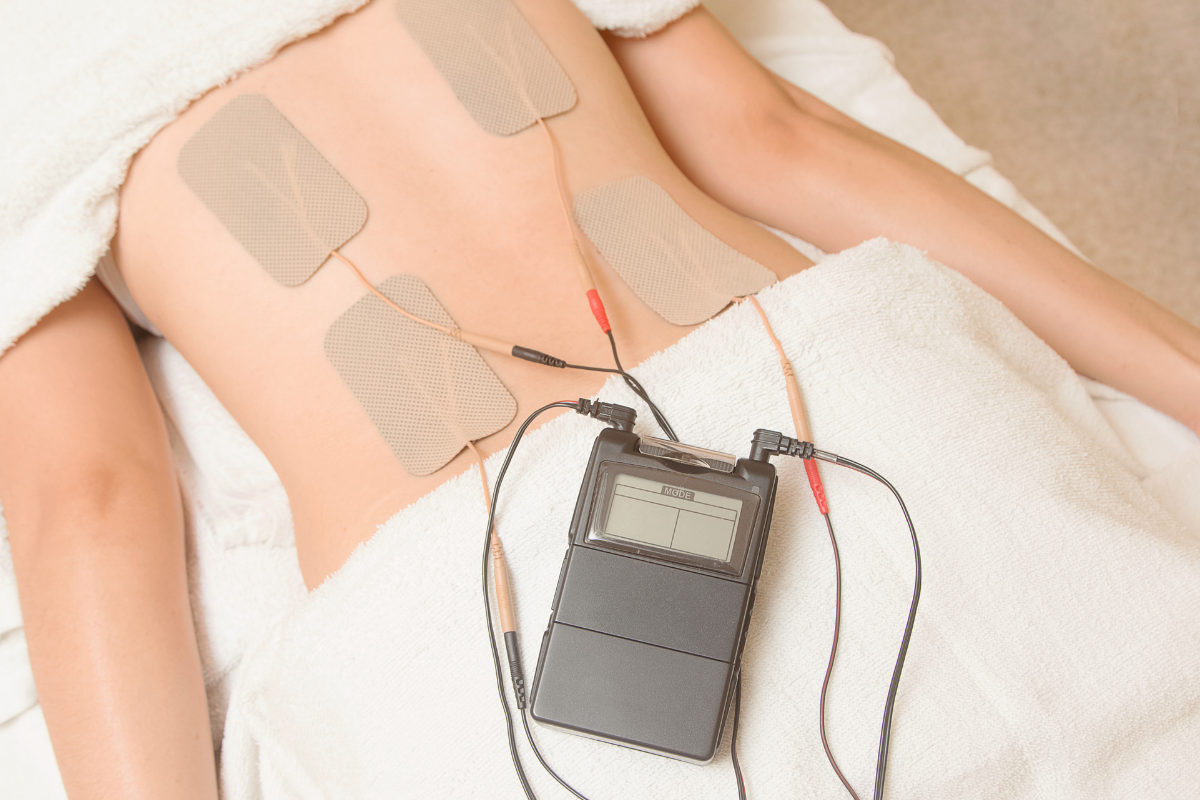

Electrical Muscle Stimulation

This treatment is designed to stop the pain cycle in your muscles to provide relief while acting as a non-drug pain reliever.

Electrical Muscle Stimulation

This treatment is designed to stop the pain cycle in your muscles to provide relief while acting as a non-drug pain reliever.